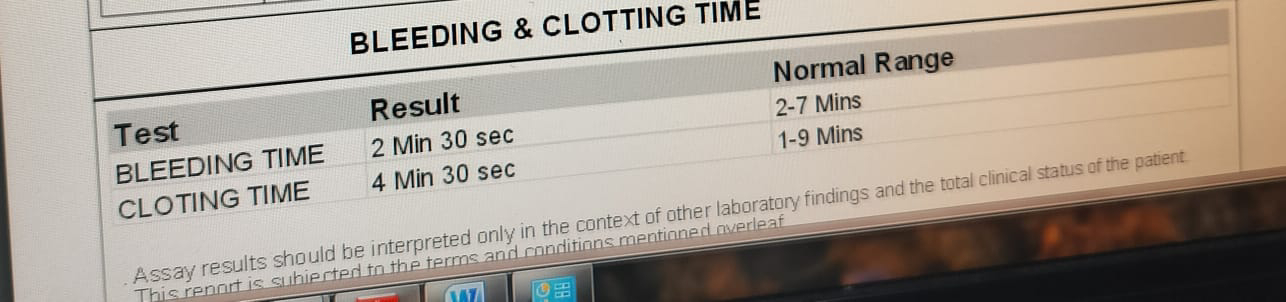

APTT 31

BLEEDING TIME :2 MIN CLOTTING TIME:4 MIN CRP:1.2 MG/DL

PT:15 SEC INR:1.11